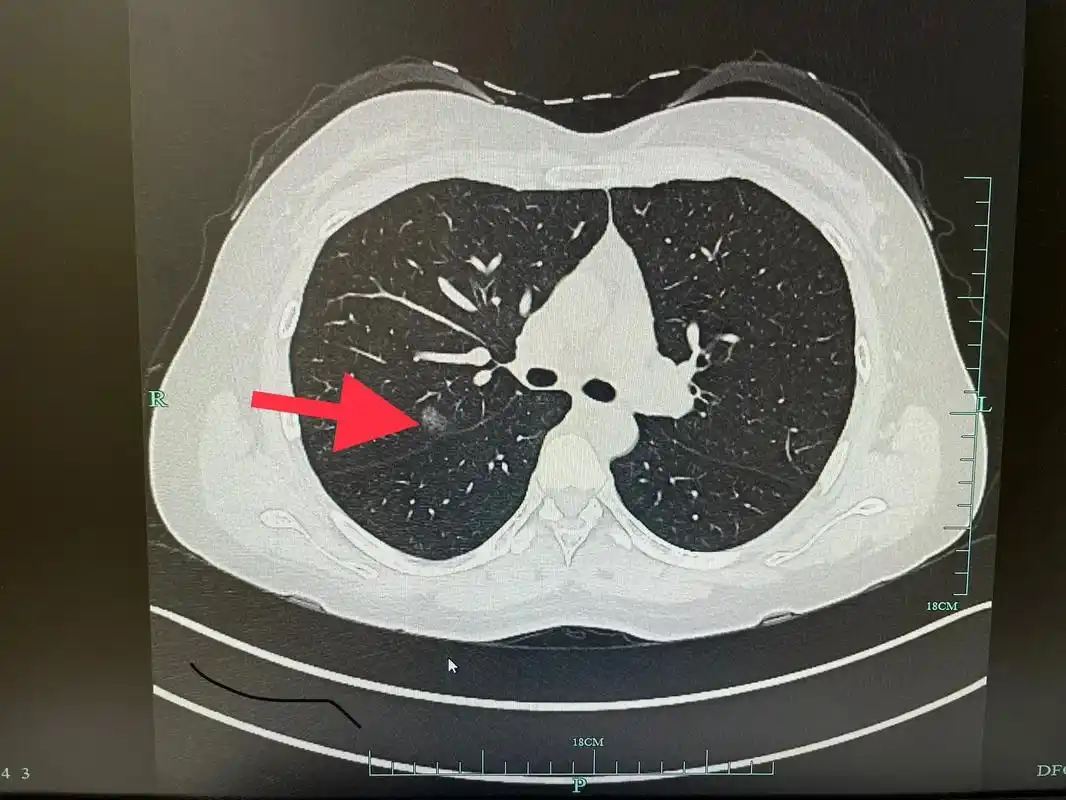

查出肺结节也不可怕,90%以上都是良性 - 抖音